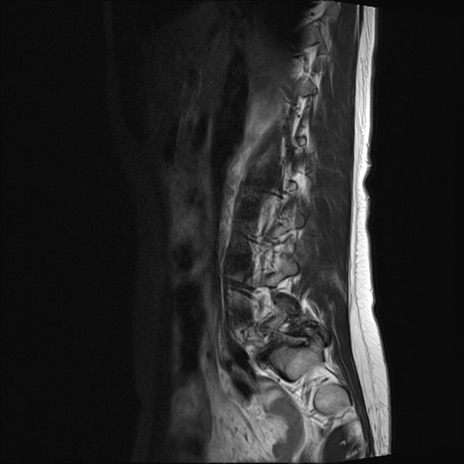

腰椎MRI

横断像と矢状断像